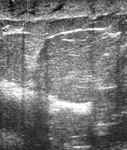

Ultrasonographic image of a fibroadenoma

Courtesy of Dr Lane Roland, University of Louisville; used with permission